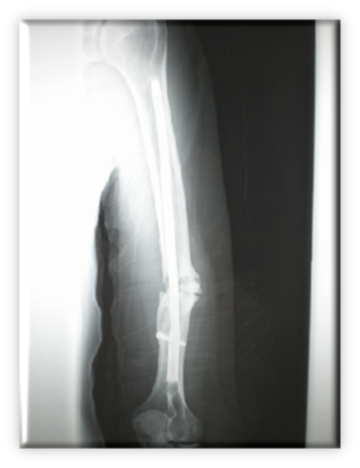

Νοσοκομείο Metropolitan General

Κάταγμα διάφυσης βραχιονίου αντιμετωπισθέν αρχικά με ανάστροφο ενδομυελικό ήλο, στη συνέχεια δυναμοποίηση του ήλου με αφαίρεση κεντρικής βίδας, τελικά όμως ψευδάρθρωση κατάγματος.